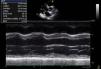

Auscultava-se sopro sistodiastólico de grau ii/vi no bordo esternal esquerdo superior não explicado pela investigação prévia. Repetiu ecocardiograma transtorácico (Figura 1) que confirmou os achados do ecocardiograma inicial. Visualizava-se, porém, um fluxo turbulento, contínuo, ao nível da bifurcação da artéria pulmonar, dirigido da aorta para o tronco e ramo direito da artéria pulmonar, evidente também na incidência supraesternal (Figuras 2–4). Foi diagnosticado canal arterial patente (CAP).

Plano paraesternal esquerdo curto eixo, nível da válvula pulmonar. Estudo com Doppler pulsado imediatamente distal à válvula pulmonar dirigido por Doppler a cor (parte superior da imagem), evidenciando fluxo sistólico transvalvular pulmonar (seta estreita) num fundo de fluxo sistodiastólico da aorta para a artéria pulmonar (seta larga).